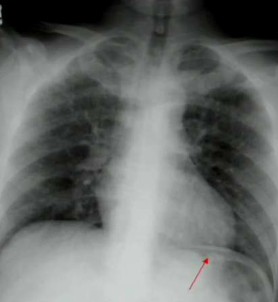

What are you looking for when you take an x-ray of a patient presenting with obstruction?

Air-fluid levels.

Free air. It typically represents a perforated ulcer or ruptured diverticulum.